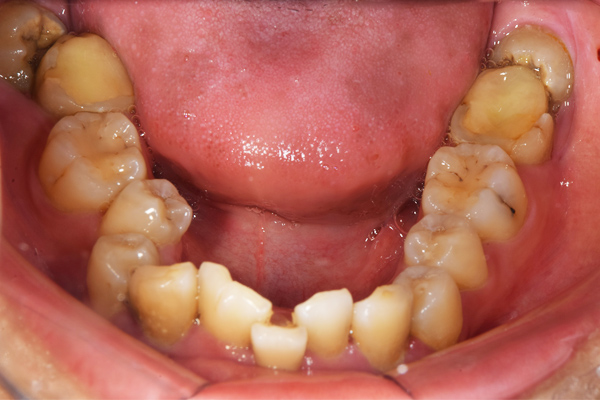

親知らずが上下4本全てに生えています。少しだけ頭が出ているような状態なのですが、歯下の2本が斜めに生えてきているようで少し痛いです。早く抜歯をしたい気持ちはあるのですが、歯医者が苦手で、大学病院などの大きな病院で全身麻酔?でやってもらおうと考えてい

ます。

上顎はしっかり親知らずがはえています。下顎は右(青)はしっかりはえていますが、虫歯になっています。下顎の左(赤)は斜めにはえています。またこちらも虫歯になっています。

親知らずは、のどに近いですし、頬っぺたもありますので、なかなか磨くのが難しいですね。そのため、虫歯になりやすい傾向にあります。また、プラーク(歯垢)除去がしずらいため、親知らずの周りの歯茎が腫れたり、出血しやすくなります。